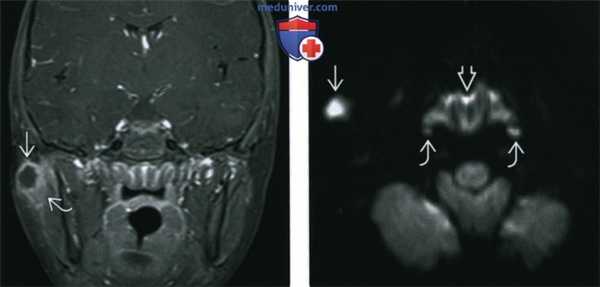

(Слева) МРТ Т1 FS c КУ, восьмилетний мальчик с отеком правой щеки. В толще околоушной железы определяется образование № с центральным участком некроза и накоплением контраста на периферии. Отмечается воспалительная исчерченность окружающей клетчатки. При аспирации был получен гной.

(Справа) MPT DWI, аксиальная проекция, этот же пациент. Снижение диффузии в центре образования, характерное для гнойного лимфаденита. Обратите внимание на реактивное увеличение лимфоидной ткани носоглотки и заглоточных лимфоузлов.

3. МРТ при нагноении лимфатических узлов:

• Т1ВИ:

о Узел с центральным участком низкоинтенсивного сигнала

о Окружающая клетчатка имеет неравномерный сигнал

• Т2ВИ:

о Узел с гиперинтенсивным сигналом (диффузным/в центре)

о Окружающие ткани, имеющие гиперинтенсивный сигнал, лучше видны в режиме FS

• DWI:

о Служит дополнением к традиционным режимам

о Диффузия в нагноившихся, некротизированных узлах снижена (яркий след DWI, темный сигнал ADC)

о По сравнению с некротизированными метастазами в лимфоузлах сигнал DWI может быть ярче, a ADC - ниже:

- Четкие критерии ADC не установлены

• Т1ВИ с контрастированием:

о Выраженное накопление контраста по периферии узла с нечеткими контурами

о В центре контраст не накапливается